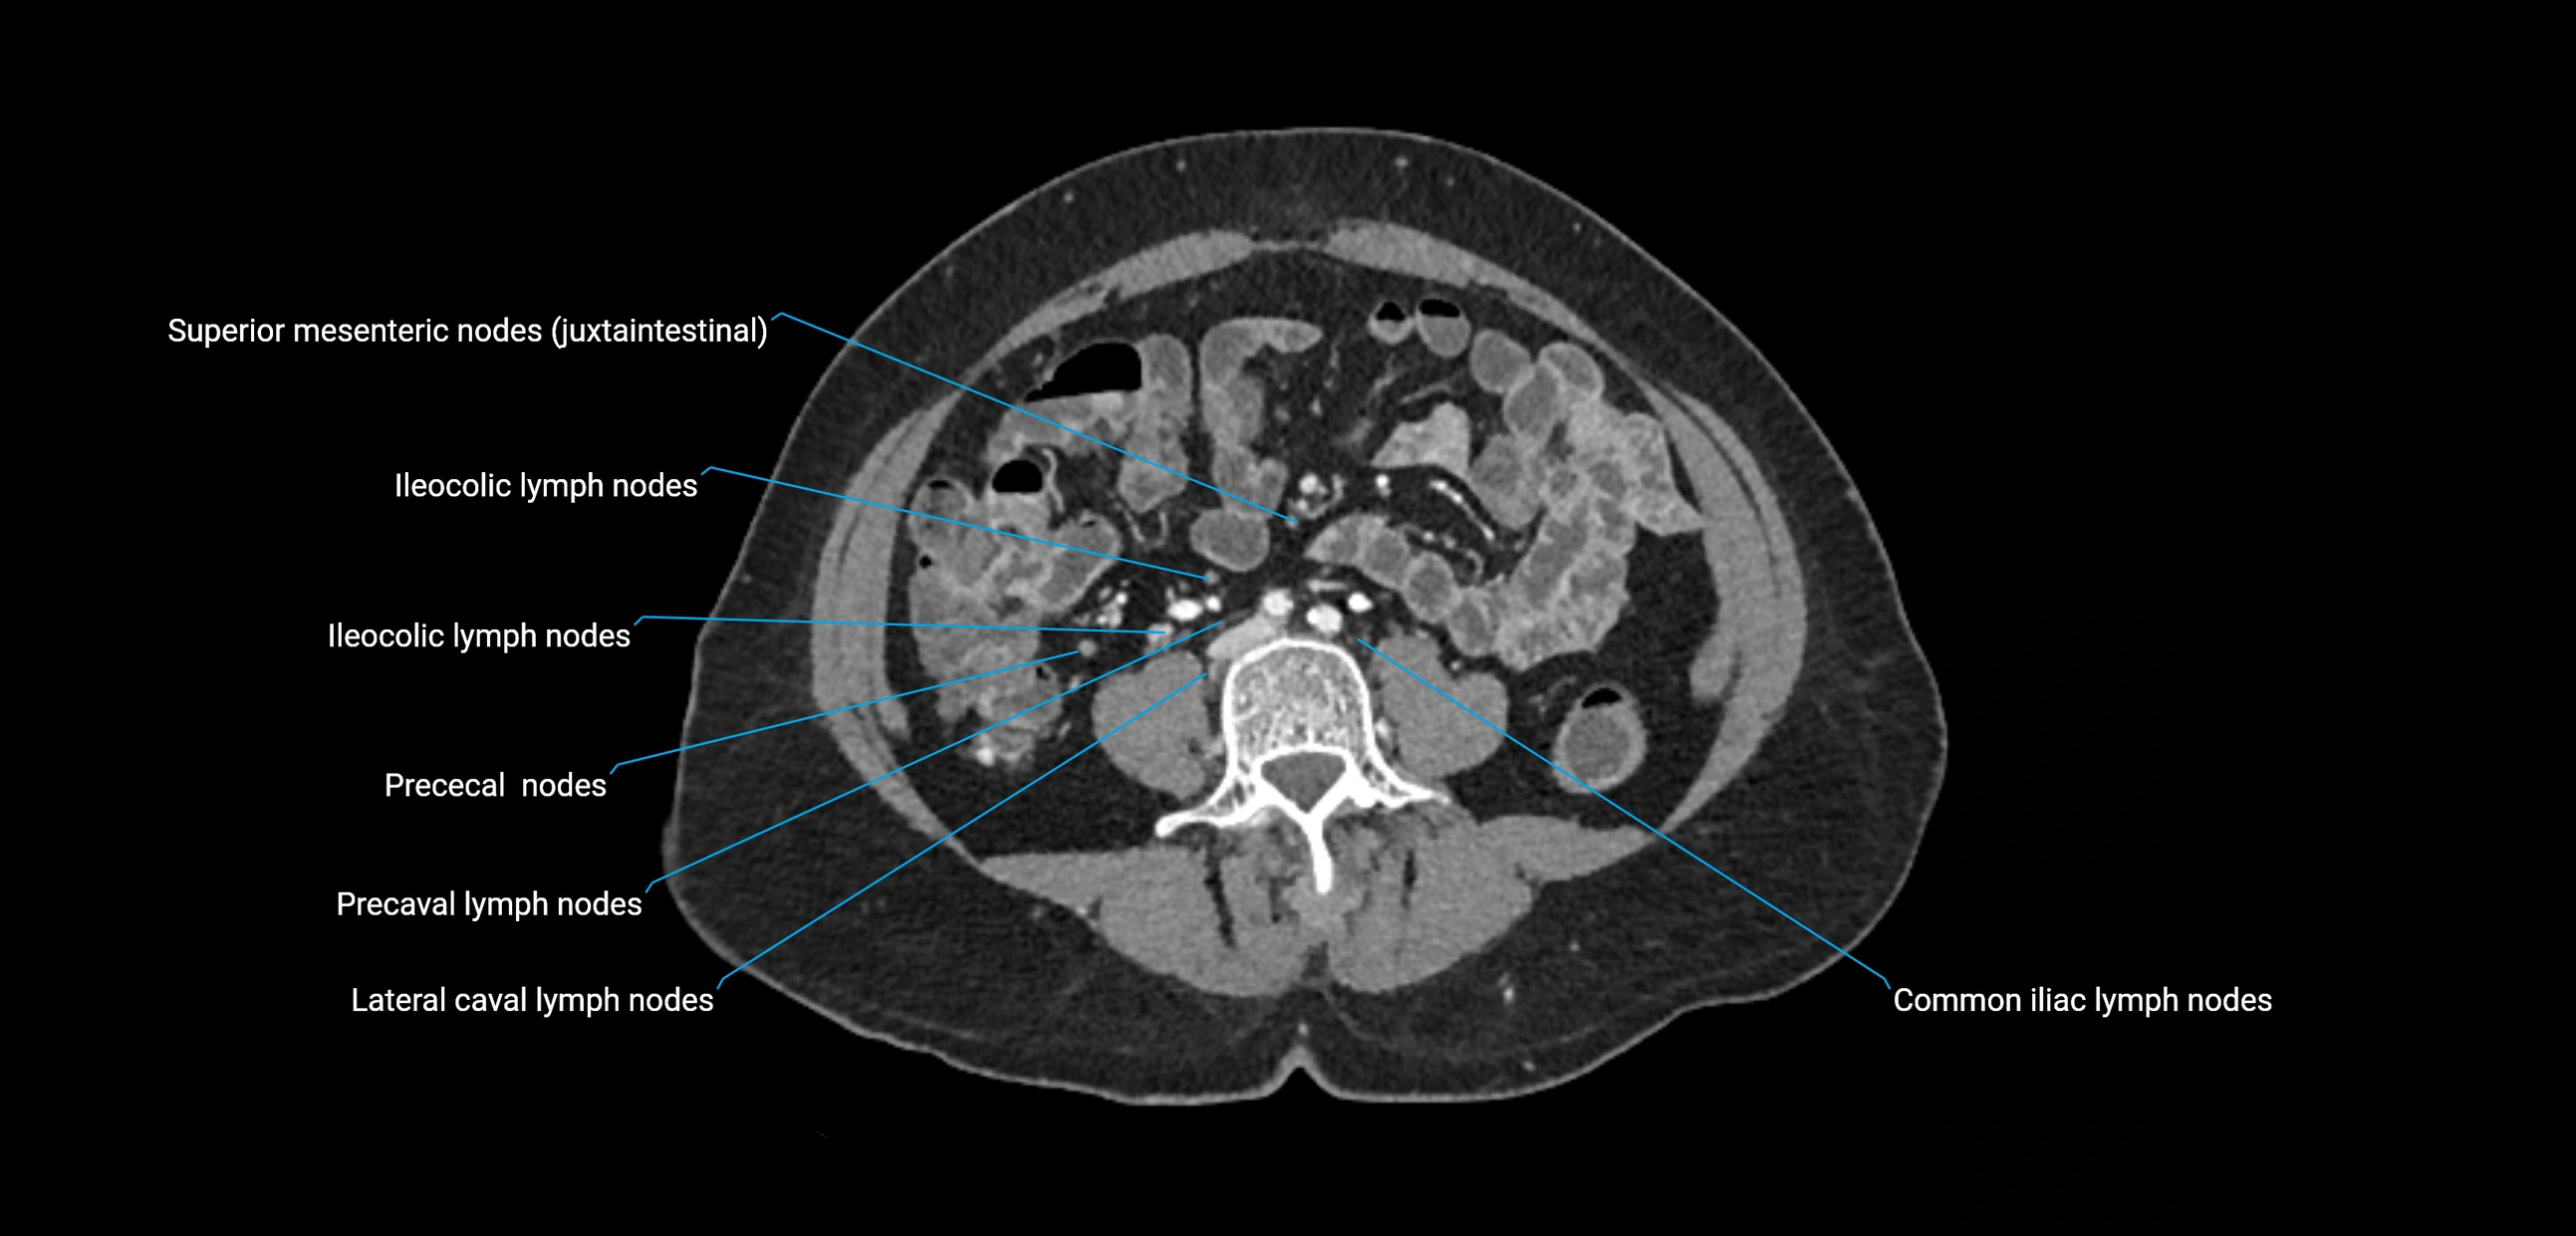

CT Appearance

CT Pre-Contrast:

• Nodes appear as soft-tissue density nodules adjacent to the aorta and IVC

• Calcification may be seen in chronic infections (e.g., tuberculosis)

CT Post-Contrast:

• Normal nodes enhance homogeneously

• Malignant nodes may show heterogeneous enhancement, central necrosis, or conglomerate formation

• Size >1 cm short axis is suspicious, though morphology and distribution are equally important

CT Venography (CTV):

• Demonstrates nodal encasement or compression of adjacent vessels (aorta, IVC, renal veins)

• Useful in staging testicular and ovarian malignancies

• Provides 3D reconstructions for retroperitoneal lymph node dissection planning

CT image

image